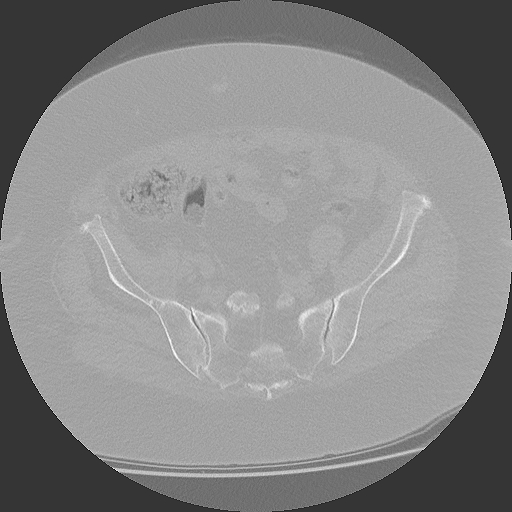

CT Becken + Überweisung zur weiteren Abklärung

04.03.2025

CT Becken mit Radiologiebefund

DICOM PDF

Aktuelles CT des Beckens mit schriftlichem Befund.

CT Becken

853 Bilder in 4 Serien | 86 MB

4 Serien verfügbar

März 2025

CT Becken + Überweisung

CT-Untersuchung mit Befund, Überweisung zur weiteren Behandlung

DICOM

CT-Untersuchung mit 4 Serien (853 Bilder)